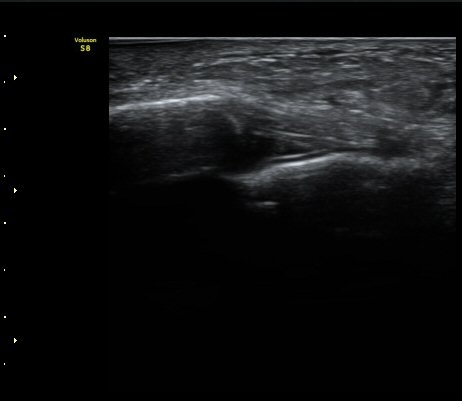

Á¾°ñÀÔ¹æ°ñÀδëÀÇ Á¾´Ü¸é°Ë»ç¿¡¼­ ÀδëÀÇ Á¾°ñ ºÎÂøºÎ ÆÄ¿­ÀÌ °üÂûµÊ(»çÁø 1, 2, 3).